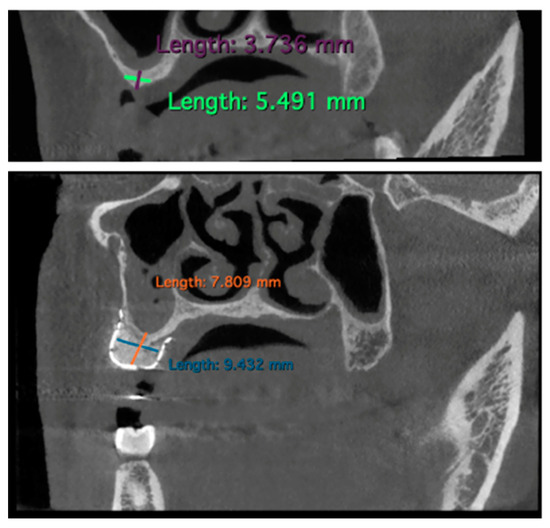

Bone gain measurements were conducted by comparing each patient’s preoperative and 6-month post-operative CBCT data.

Specifically, parasagittal images of the respective CBCTs were used as a reference for measuring bone defects. Mandibular bone defects were measured from the lower margin of the inferior alveolar nerve to the coronal portion of the bone defect. This approach aimed to prevent titanium mesh radiopacity from influencing post-operative result measurements, ensuring a complete identification of the inferior alveolar nerve.

The measurements were performed by using the software Horos Viewer™ (v.4.0.1) as shown in Figure 3.

Figure 3. Example of measurements performed on CBCT using the Horos Viewer™ software: pre-intervention and 6 months post-GBR (case n.10).